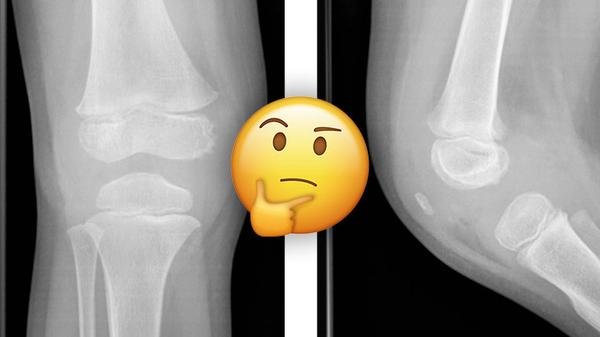

Bebeklerin Diz Kapakları Röntgen Filminde Neden Görünmez?

Bebeklerin diz kapakları oluşum süreci, biz yetişkinlerde olduğundan farklıdır. Bebekler doğduklarında kemikli bir diz kapağına sahip değildirler. Diz kapakları sadece kıkırdaktan oluşur ve zamanla kemik formunu alırlar. Bu kıkırdak yapı, zamanla birleşerek kemiksi hale gelir. Bu süreç sonunda bebekler de kemikli diz kapaklarına sahip olurlar. Bebeklerde diz kapakları röntgen filmi sırasında görünmez çünkü kıkırdak dokuda kan damarları veya sinir bulunmaz. Bu nedenle kıkırdak hücrelerinin beslenmesi ve zararlı maddelerin uzaklaştırılması sadece difüzyon yoluyla gerçekleşir. Bu süreç, bebeklerin hareketlendiği ve emeklemeye başladığı dönemlerde başlar ve 10-12 yaşlarına gelindiğinde tamamlanır. Uzmanlar, bu dönüşüm sürecinde dikkat edilmesi gerektiğini ve bebeğin diz kapaklarına yüklenen stresin ve yaralanmaların önlenmesi gerektiğini vurgular. 1. #BebeklikDönemi 2. #DizKapakları 3. #BebekSağlığı 4. #KemikGelişimi 5. #BebekBakımıİnternet Hız Testi